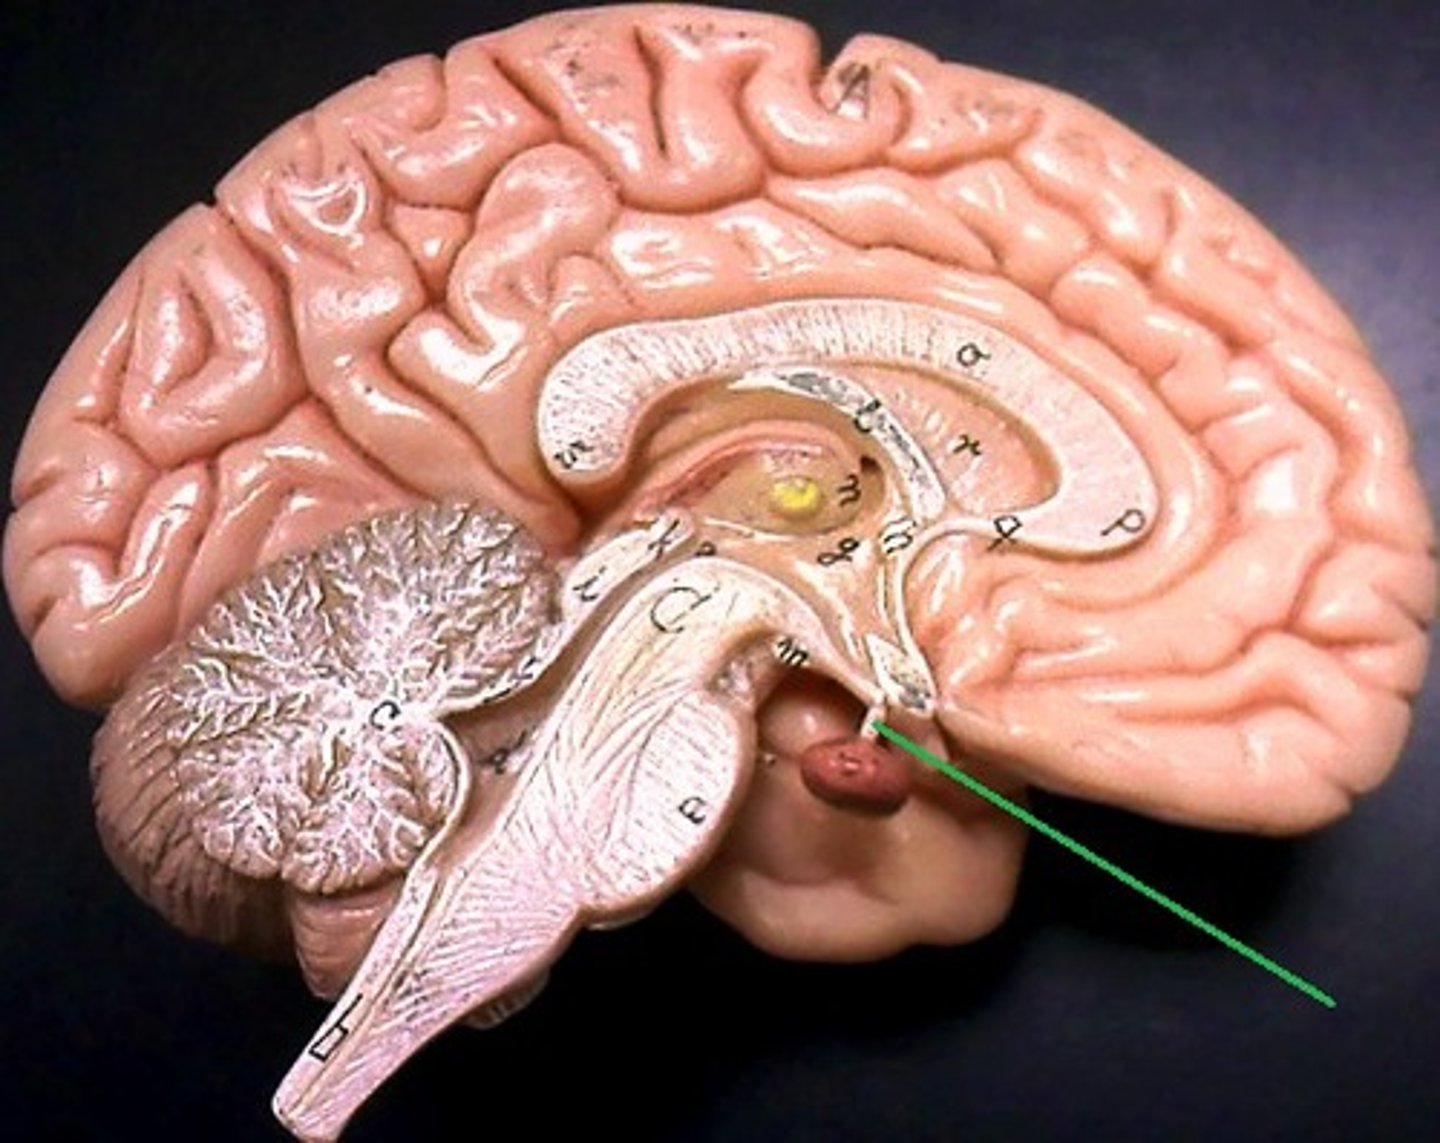

brainstem

cerebellum

cerebrum

hypothalamus

medulla oblongata

midbrain

pons

thalamus

corpus callosum

fornix

cerebral aqueduct (brainstem)

corpora quadrigemina (brainstem)

fourth ventricle

hypophysis (pituitary gland)

infundibulum

intermediate mass of thalamus

pineal gland

choroid plexus (of ventricles)

third ventricle